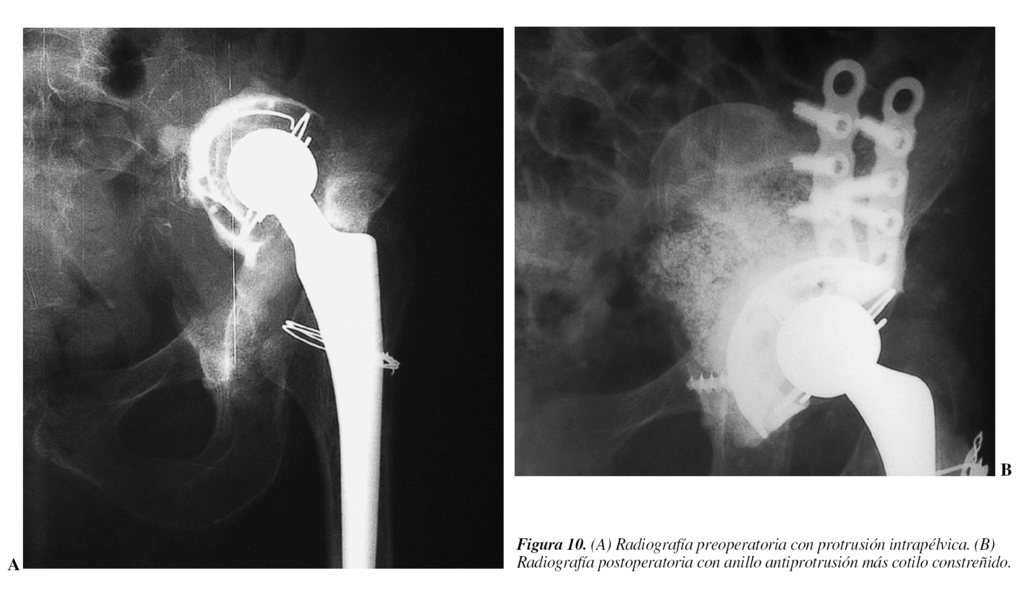

Los primeros se caracterizan además porque la cabeza protésica se encuentra más penetrada de lo normal y por consiguiente, al no disponer de ningún mecanismo de estrangulación, son los que determinan menor constricción (figs. 8, 9 y 10).

A favor

Se produce una estabilidad inmediata; es una técnica sencilla, que incluso permite mantener el cotilo metálico en su posición, sobre todo si está firme, y cementar un inserto constreñido.

Las publicaciones refieren porcentajes entre el 67 y el 96% de resultados favorables.

Resultados

Goetz et al32 reportan 53 caderas (tripular constreñido) con más del 90% de buenos resultados a dos años.

Anderson, Murray y Skinner33 comunican 18 caderas (cotilo constreñido con mecanismo de bloqueo) con un 67% de resultados favorables.

Los fracasos posibles se pueden presentar en cualquiera de las tres intercaras: a) inserto-cotilo metálico; b) cabeza-inserto y c) mecanismo de bloqueo.

En contra

No todos los cotilos constreñidos proporcionan igual cantidad de constricción.

El rango de movilidad de la mayoría de los cotilos constreñidos, antes del choque entre el cuello y el inserto, es pequeño.

Se produce un aumento del desgaste del polietileno.

Una complicación no frecuente es la disociación cono-cabeza, siendo necesaria la reducción abierta y aumentar la longitud del cuello con o sin faldón (fig. 11).

Existe la posibilidad de fracaso en las dos intercaras entre el cotilo metálico y el hueso y entre el cotilo metálico y el inserto debido a la transmisión de cargas excesivas a estas dos intercaras.

Habitualmente, si la cadera se vuelve a luxar, al quedar la cabeza aprisionada y constreñida o fuera del inserto, es necesaria la cirugía abierta, aunque tenemos dos casos en los que se ha podido evitar la cirugía, siendo favorable la reducción cerrada.